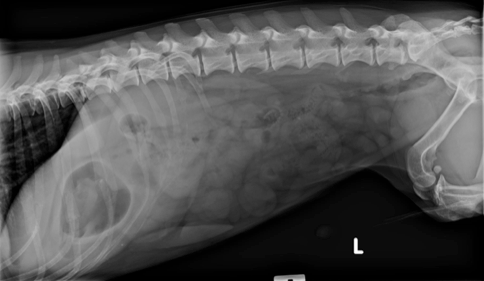

In addition your veterinarian may recommend blood and urine tests to assess whether the patients health has been compromised by the obstruction or to rule-out other. This allows improved visibility of the urinary bladder as well as the distal aspect of the penile urethra. Several views or a series of specialized X-rays using contrast material barium or other radiographic dye will often be necessary. If a foreign body becomes stuck at any point in the digestive tract from the mouth to the esophagus stomach or intestines so that it partially or completely blocks the flow of nutrients and impairs blood flow to the bowel then the foreign body becomes a life-threatening obstruction. In the second lateral radiograph the pelvic limbs are pulled. More often than not ultrasound is our first line of investigation when dealing with abdominal cases.

Veterinary Medical and Surgical Group San Juan. Young cats and young large-breed dogs are more likely to present with signs of foreign body obstruction than older animals. Often the foreign body cannot be seen on the x-ray but the consequences of the foreign body obstruction are visible. Clinical signs are variable depending on duration degree and location of the foreign body but often include vomiting and anorexia. Gastrointestinal foreign bodies are an important differential diagnosis for patients presented for vomiting and radiography remains the main initial imaging modality in these cases.

In most cases a veterinarian will assess the dogs condition with X-rays or other imaging scans to determine the safest and most effective approach. Gastric foreign body is a term that refers to any material other than food that is eaten and that results in a serious digestive problem in the stomach. If a foreign body becomes stuck at any point in the digestive tract from the mouth to the esophagus stomach or intestines so that it partially or completely blocks the flow of nutrients and impairs blood flow to the bowel then the foreign body becomes a life-threatening obstruction. The string may cut through the frenulum of the tongue and bury. Often the foreign body cannot be seen on the x-ray but the consequences of the foreign body obstruction are visible.

Gastric foreign body is a term that refers to any material other than food that is eaten and that results in a serious digestive problem in the stomach. Your veterinarian will make recommendations and if this is the case may also suggest. For objects stuck in the esophagus an endoscopy may be done to remove the object. The object also may be removed through endoscopy in which a long tube is inserted through the mouth of your dog and is used to pull the object from the stomach. These include fluid and gas building up behind or within the foreign body.